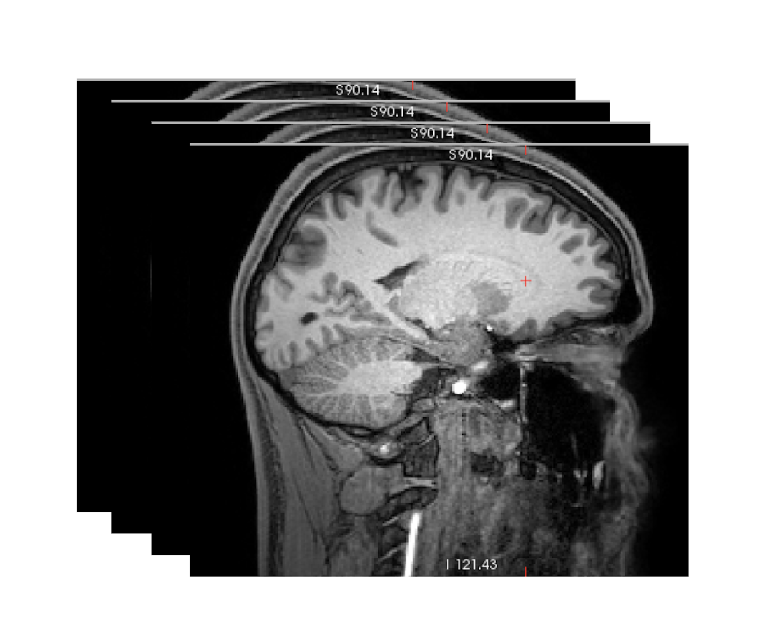

DICOM files serve as the only require input data to start the pipeline. Required T1w and optional T2w.

3D volumetric NIfTI file is created using dcm2niix software from DICOMs.